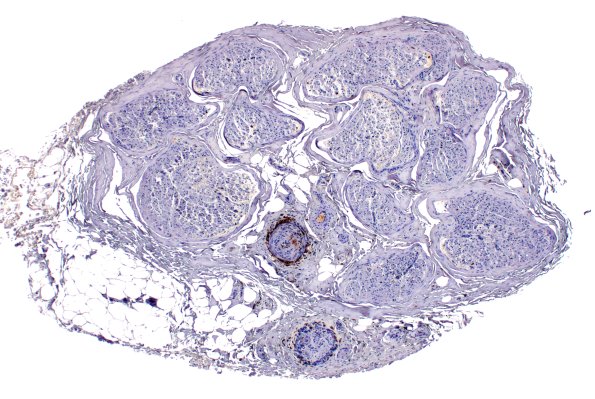

Washington University Experience | PERIPHERAL NEUROPATHY | 11 VASCULITIS - VASCULOPATHY | 4 Polyarteritis nodosa | 11C1 PAN (Case 11) CD45 4X

11C1-3 Leukocyte common antigen immunohistochemistry demonstrates a persistent perivascular inflammatory infiltrate. (CD45 IHC)